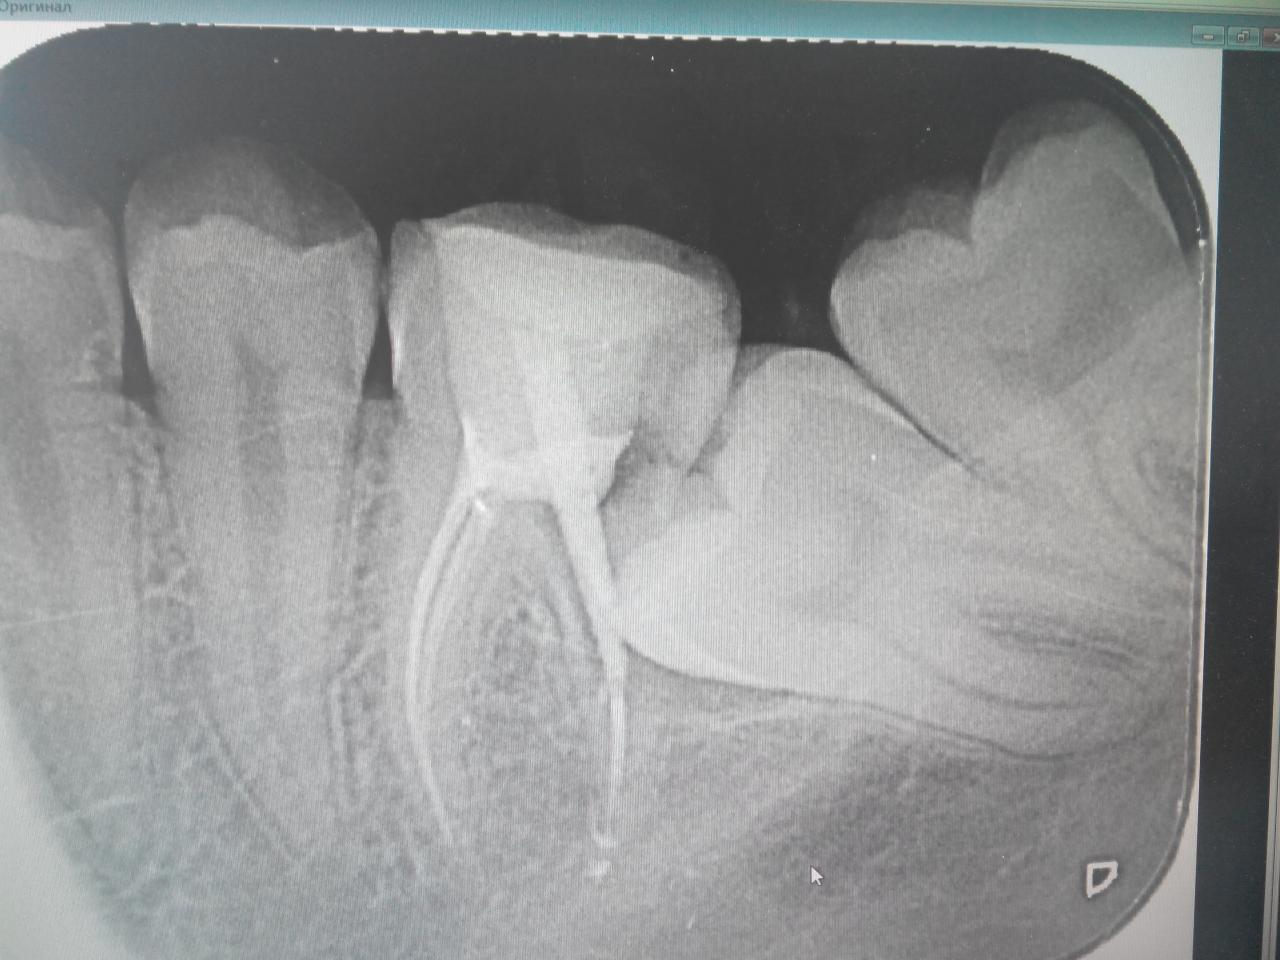

Нажмите на изображение для увеличения

Название: GLE1uz4dWAw.jpg

Просмотров: 27

Размер:	204.1 Кб

ID:	9897685

Подскажите что делать в таком вот случает. Врачи разное говорят, то удалять оба, то один, то лечить соседний зуб ибо там карьес и пусть так будет если не беспокоит

Да уж, вы действительно удивительное чудо).

Я бы удалила, условий для полноценной гигиены нет, поэтому исход один. Кариес в восьмом уже приличный, лечение каналов в таких условиях очень затруднительное, то есть качественно не получится. То есть опять приходим к удалению, но перед этим еще вкладываем в эти зубы деньги, здоровье и время. И на верхний пятый тоже обратите внимание.

я всегда считала что у меня 7 зуб просто не вылез, а он оказался под 8-м (((

да в 8-м карьес и в 6-м сказали тоже и что надо если пытаться сохранять то пломбировать каналы в обоих, но потом через н-ное кол-то лет все равно удалять.

Может и лучше конечно сразу удалить 8-й, а с 7-м что тогда? тоже удалять? ((

похоже еще как))))

перемещение зубов? это мне не предлагали. Понятия не имела что такое делают